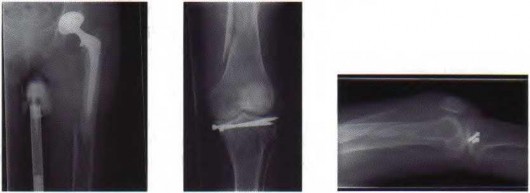

Question 10:

A 35-year-old male sustains a vertically oriented (Pauwels type III) basicervical femoral neck fracture. Which of the following fixation constructs offers the highest biomechanical stability for this specific fracture pattern?

Options:

- Three parallel cancellous screws

- Sliding hip screw (SHS) alone

- Sliding hip screw with an anti-rotation screw

- Cephalomedullary nail

- Dynamic condylar screw

Correct Answer: Sliding hip screw with an anti-rotation screw

Explanation:

Vertical fracture patterns (Pauwels III) experience high shear forces. A sliding hip screw (SHS) provides better resistance to vertical shear compared to cancellous screws. The addition of an anti-rotation (derotational) screw superior to the SHS provides optimal stability.